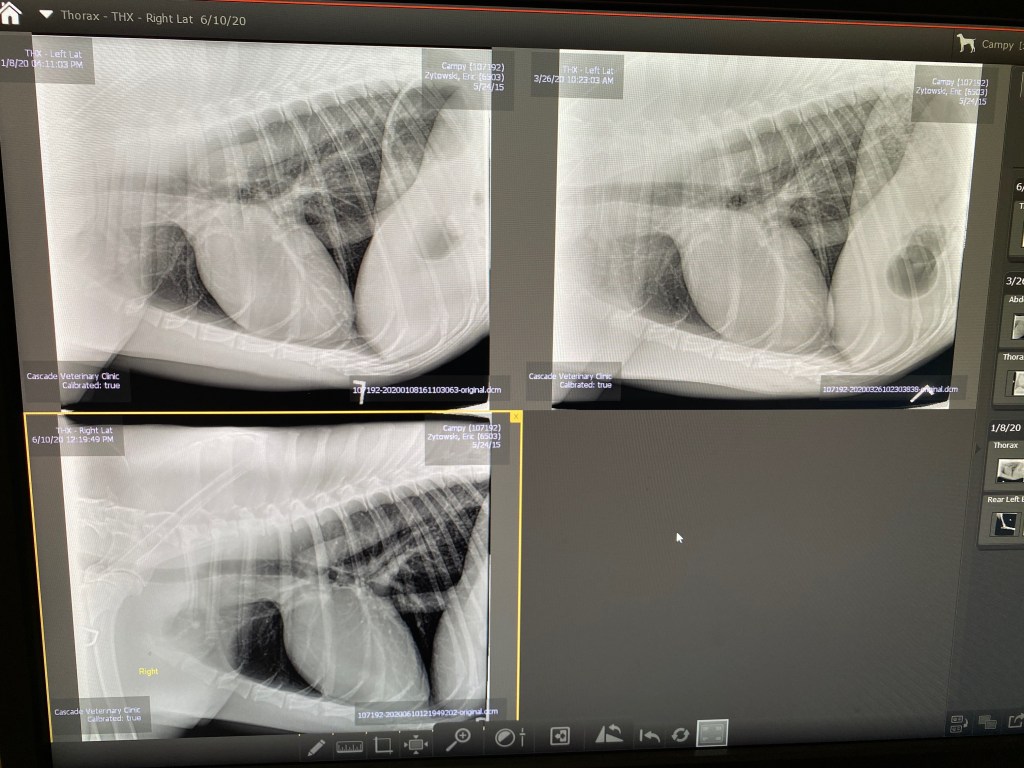

I had our vet take another set of chest X-rays. Unfortunately, they show an ominous spot on his lung that wasn’t there in the last two X-rays taken in January and March. This is really soul-crushing news. Campy had been doing so well up until now.